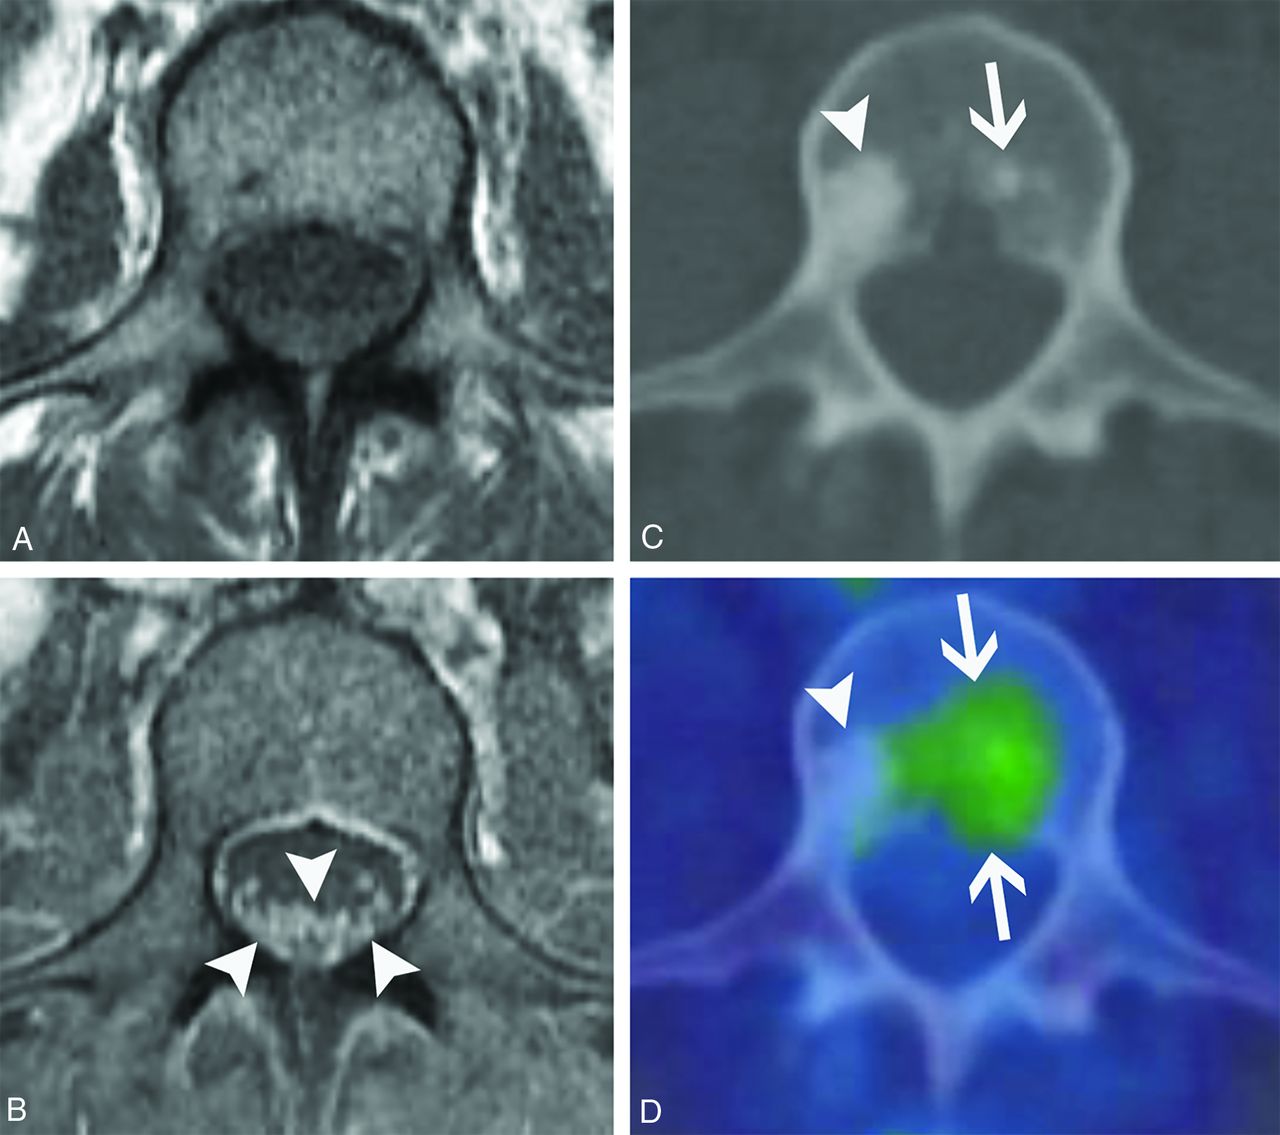

Reports of imaging findings of paraneoplastic polyneuropathy involvement are scarce. To our knowledge, there are only 5 published cases of paraneoplastic polyneuropathy showing cauda equina abnormalities. These have demonstrated variable patterns of enhancement, with 2 patients having ANNA-1 positivity.27,29-32 We have found that enhancement can predominantly involve the dorsal (Fig 8) or ventral nerve roots (Fig 9), and the pattern of enhancement does not always correlate with symptoms. The clinical presentation can frequently mimic Guillain-Barré syndrome with a similar rapidly ascending weakness (Fig 8). Additionally, polyneuropathy may be seen with osteosclerotic multiple myeloma in the setting of POEMS syndrome (polyneuropathy, organomegaly, endocrinopathy, monoclonal plasma proliferative disorder, skin changes).33 Although POEMS syndrome is not always described among the classic forms of PNS, many authors consider its peripheral nerve involvement to be paraneoplastic. The presence of sclerotic bone lesions and peripheral nerve root enhancement are the most important imaging features to suggest POEMS syndrome (Fig 10).

POEMS syndrome. A 50-year-old woman presented with weakness, burning, and tingling in her extremities that had waxed and waned over 4 years. Axial T1-weighted pre- (A) and postcontrast (B) images from her lumbar spine MR imaging show diffuse enlargement and enhancement of the cauda equina nerve roots (B, arrowheads). Axial CT (C) and fused FDG-PET/CT (D) images show a non–FDG-avid lumbar vertebral sclerotic lesion (C and D, arrowheads) and an adjacent mildly FDG-avid sclerotic lesion (C and D, arrows). After additional work-up, she was diagnosed with osteosclerotic multiple myeloma, which is characterized by osteosclerotic lesions with variable FDG avidity. Her MR imaging findings were ultimately attributed to polyneuropathy in the setting of POEMS syndrome.